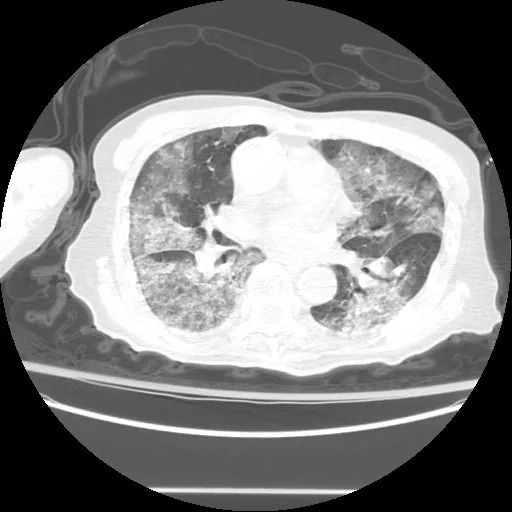

随着我国疫情防控政策变化和新一波新冠感染高峰的到来,“白肺”一词引起了大家的极大关注。感染新冠病毒以后,病毒主要攻击患者的上呼吸道,患者会出现咳嗽症状,如病毒通过上呼吸道进入下呼吸道,就会感染患者肺部,出现肺炎,严重者出现“白肺”,伴随着咳嗽症状。

很多患者非常担心自己和家人是不是也得了“白肺”?纷纷到各大医院进行CT检查,就我院来说,每个院区每天检查约三百人次,都能检查出很多“白肺”患者。

首先,我们要明白咳嗽和肺炎的区别,不是所有咳嗽的患者都得了肺炎,咳嗽仅仅是一种症状,感染新冠病毒以后,很多患者会出现咳嗽,这是人体的保护机制,通过咳嗽和咳痰将体内的分泌物排除。而一部分患者,病毒会通过上呼吸道进入下呼吸道,感染肺部,出现肺炎,严重者甚至出现“白肺”。